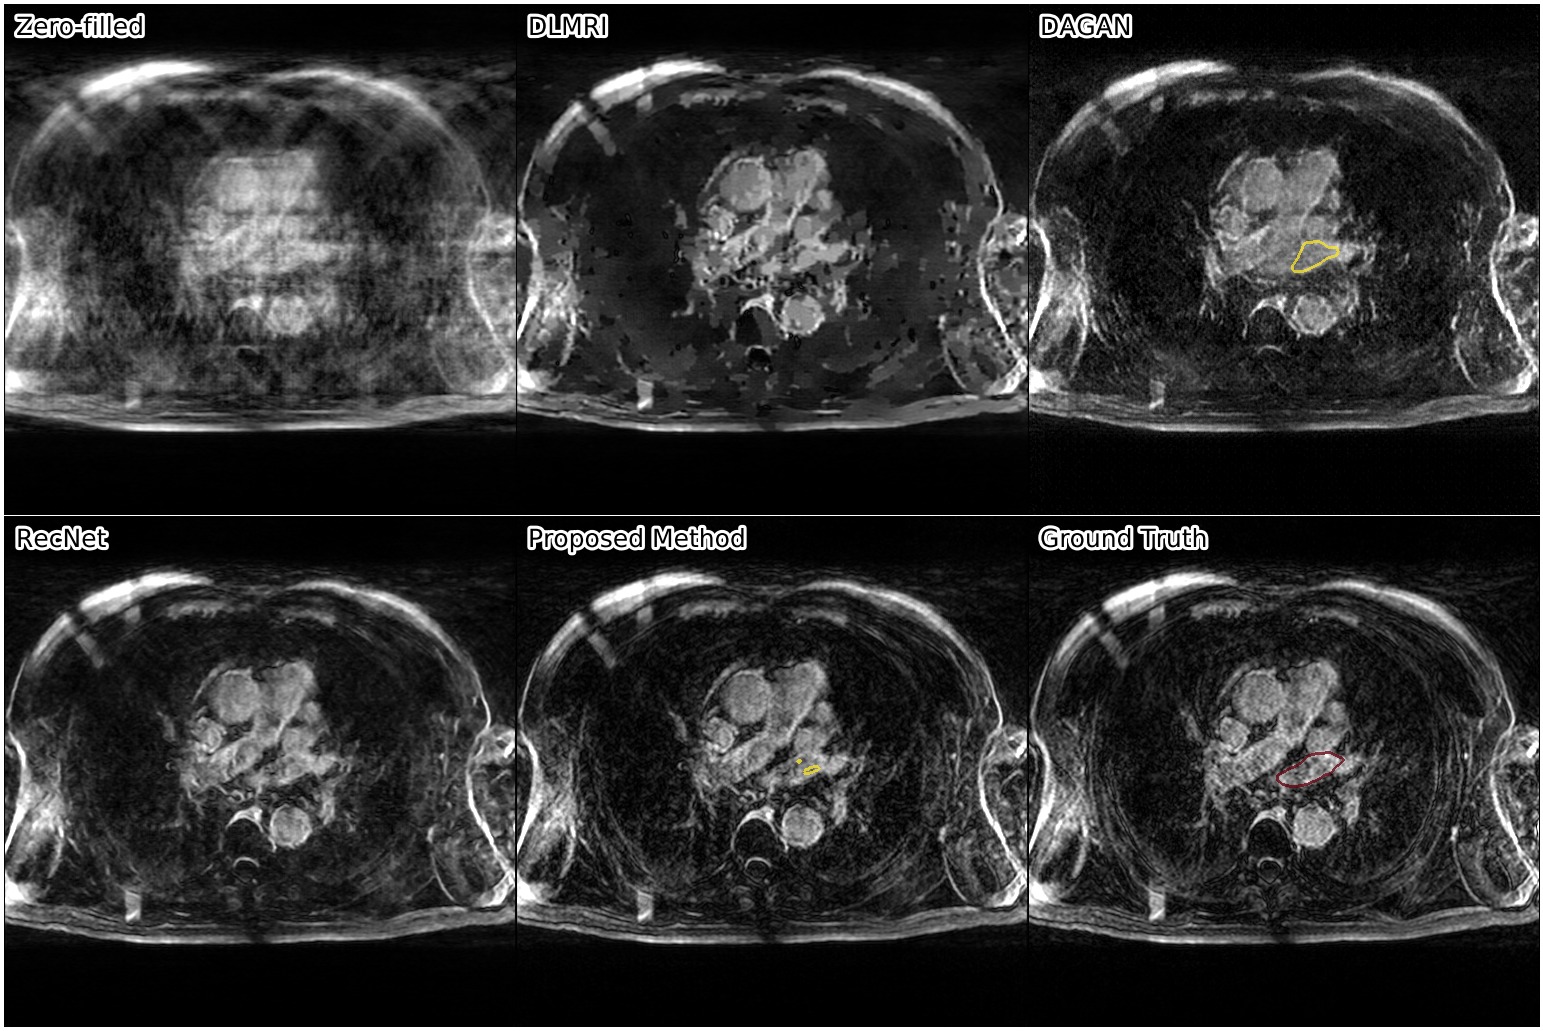

Results. We compared our approach against three other reconstruction methods: RecNet111https://github.com/js3611/Deep-MRI-Reconstruction [14] (i.e. the proposed approach without refinement step), DAGAN222https://github.com/nebulaV/DAGAN [16] using both adversarial and perceptual loss, and DLMRI333http://www.ifp.illinois.edu/~yoram/DLMRI-Lab/DLMRI.html [10], a dictionary learning based method. No data augmentation was used for any of the methods.

We show the results of our evaluation in Table 1, and a sample reconstruction in Figure 2. RecNet performed best in terms of PSNR, which is expected as its training objective directly corresponds to this metric, but its reconstructions were over-smoothed. DLMRI had the lowest MOS, with its reconstructions showing heavy oil paint artifacts. DAGAN, combining MSE loss with a visual loss function without any further precautions, suffered from low PSNR. While its reconstructions also looked sharp, they were noisy and often displayed aliasing artifacts, which was reflected in a lower MOS compared to our method. Our proposed approach achieved significantly444Significance determined by a two-sided paired Wilcoxon signed-rank test at . higher mean opinion score than all other methods, while still maintaining high PSNR. Reconstructions obtained by our method appeared sharper with better contrast. Moreover, our method achieved the highest SIS close to segmentation performance on the ground truth data, which indicated that the segmented objects were clearly visible in the reconstructed images.

These results further demonstrate that PSNR alone is a subpar indicator for reconstruction quality, making our SIS a useful supplement to those metrics. For our method, SIS agreed with the quality score given by the expert user. Somewhat surprising is that the SIS of DLMRI is slightly higher than RecNet and DAGAN although DLMRI has the worst MOS. We conjecture this is because, although DLMRI reconstructed images lack textural details, areas belonging to the same organ have similar intensity values, which helps the segmentation task. While scoring through an expert user is thus still the safest way to evaluate reconstructions, we believe that in conjunction with PSNR, SIS is a helpful tool to quickly judge image quality during the development of new models.

The following images show more samples for 8-fold undersampling. For each of the seven patients of the test set, a random slice showing the left atrium was selected. The contour of the predicted segmentation of left atrium is shown in yellow, the contour of the ground truth segmentation in red.